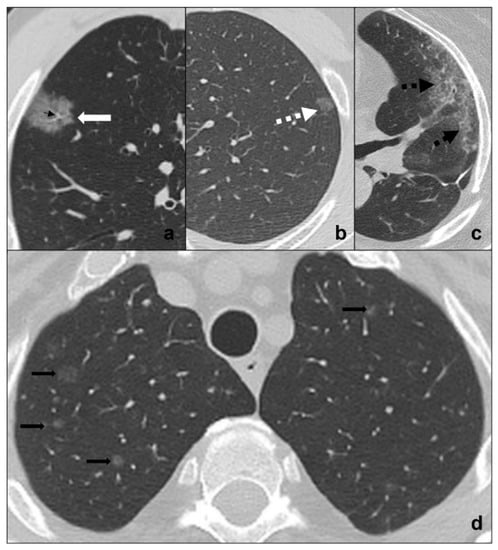

- Early phase or phase one (between day 0 and day 4) is characterized by bilateral and diffuse subpleural ground-glass opacities (Figure 1a);

- Progressive phase or phase two (between day 5 and 8) shows extensive subpleural crazy paving areas co-existing with ground-glass opacities. Small consolidative foci may be present (Figure 1b);

- Peak phase or phase three (between day 9 and 13) is defined by subpleural consolidation with peripheral ground glass and/or crazy paving opacities (halo sign) (Figure 1c);

- peripheral pulmonary vessels ectasis, especially within ground-glass/crazy paving opacities (Figure 2a);